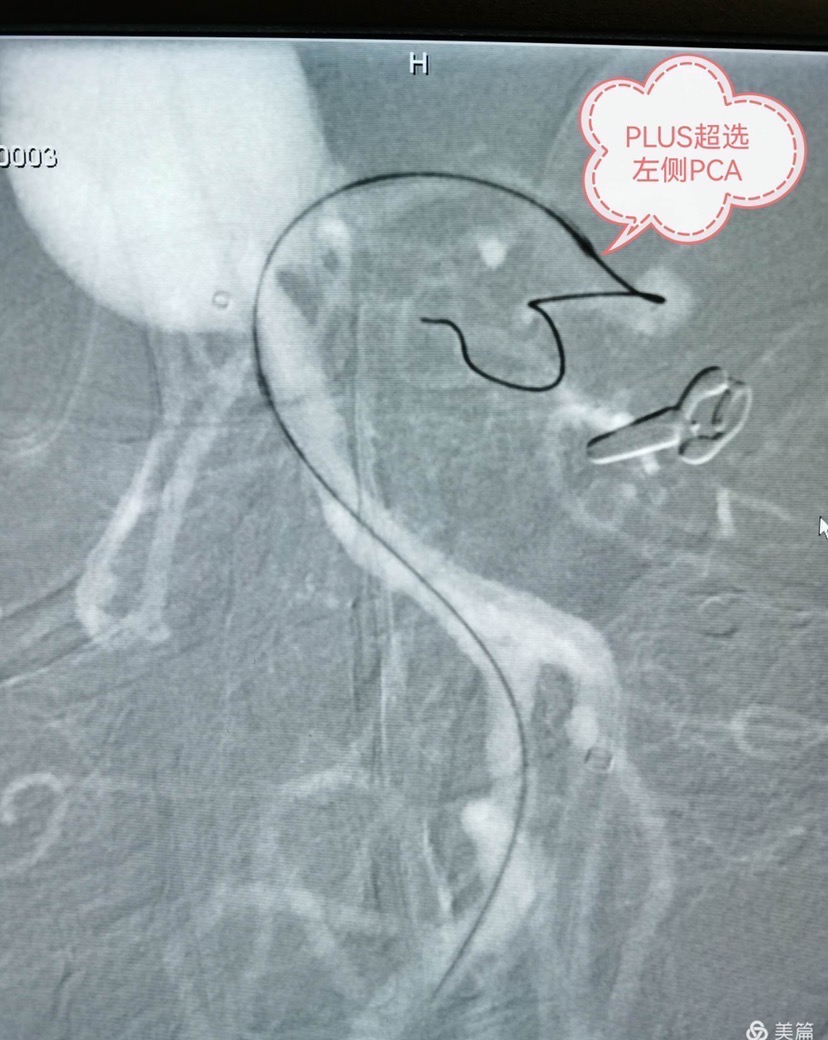

换第二个工作角度,prowlerplus微导管顺利超选至左侧大脑后动脉远端,echelon栓塞导管置于瘤腔内。